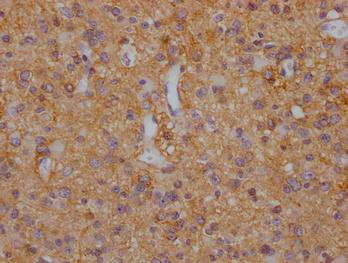

IHC image of CSB-PA021434LA11HU diluted at 1:200 and staining in paraffin-embedded human glioma cancer performed on a Leica BondTM system. After dewaxing and hydration, antigen retrieval was mediated by high pressure in a citrate buffer (pH 6.0). Section was blocked with 10% normal goat serum 30min at RT. Then primary antibody (1% BSA) was incubated at 4°C overnight. The primary is detected by a Goat anti-rabbit polymer IgG labeled by HRP and visualized using 0.05% DAB.